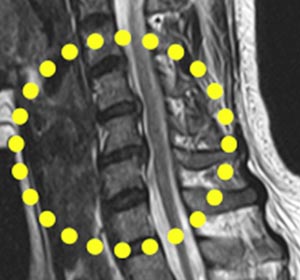

목디스크 증상 상지 방사통

터진 디스크가 팔로 내려가는 신경을 자극하여 어깨부터 팔꿈치, 팔뚝, 손까지 저리고 당기고 아픕니다.

목디스크 증상 마비

손상된 디스크가 팔로 내려가는 신경을 자극하여 쥐는 힘이 떨어져 물건을 잘 놓치거나 팔을 들어 올리기가 힘들어집니다.

목디스크 증상 뒷목 결림

뒷목이 뻣뻣하고 쑤시며 결리는 통증이 나타납니다니다. 목의 디스크는 머리를 받쳐주고 고개를 숙이거나 젖힐 때, 좌우로 돌릴 때 관절 역할을 시행하는 이 디스크가 손상을 입으면 뒷목과 어깨 쪽에 통증이 등장하고.

목디스크 증상 두통

목에서 뇌로 가는 혈관과 신경이 압박되어 혈액순환이 순조롭지 않아 지면 산소부족 현상으로 두통이 나타나고다. 오랜 시간 방치하면 뇌혈관에 문제가 일어날수 있으니까 두통이 연속된다면 빠른 시일 내에 병원에 병원 방문해 보는 것이 좋다고 합니다.

목디스크 증상 목 통증

목디스크가 파열돼서 신경을 자극하면 고개를 젖히거나 돌리기도 참 어려워지며 통증이 발생하고요. 통증은 견갑골 안쪽까지 내려가 등 쪽 깊은 곳까지 쑤시고 찌르는 듯한 통증이 생깁니다.